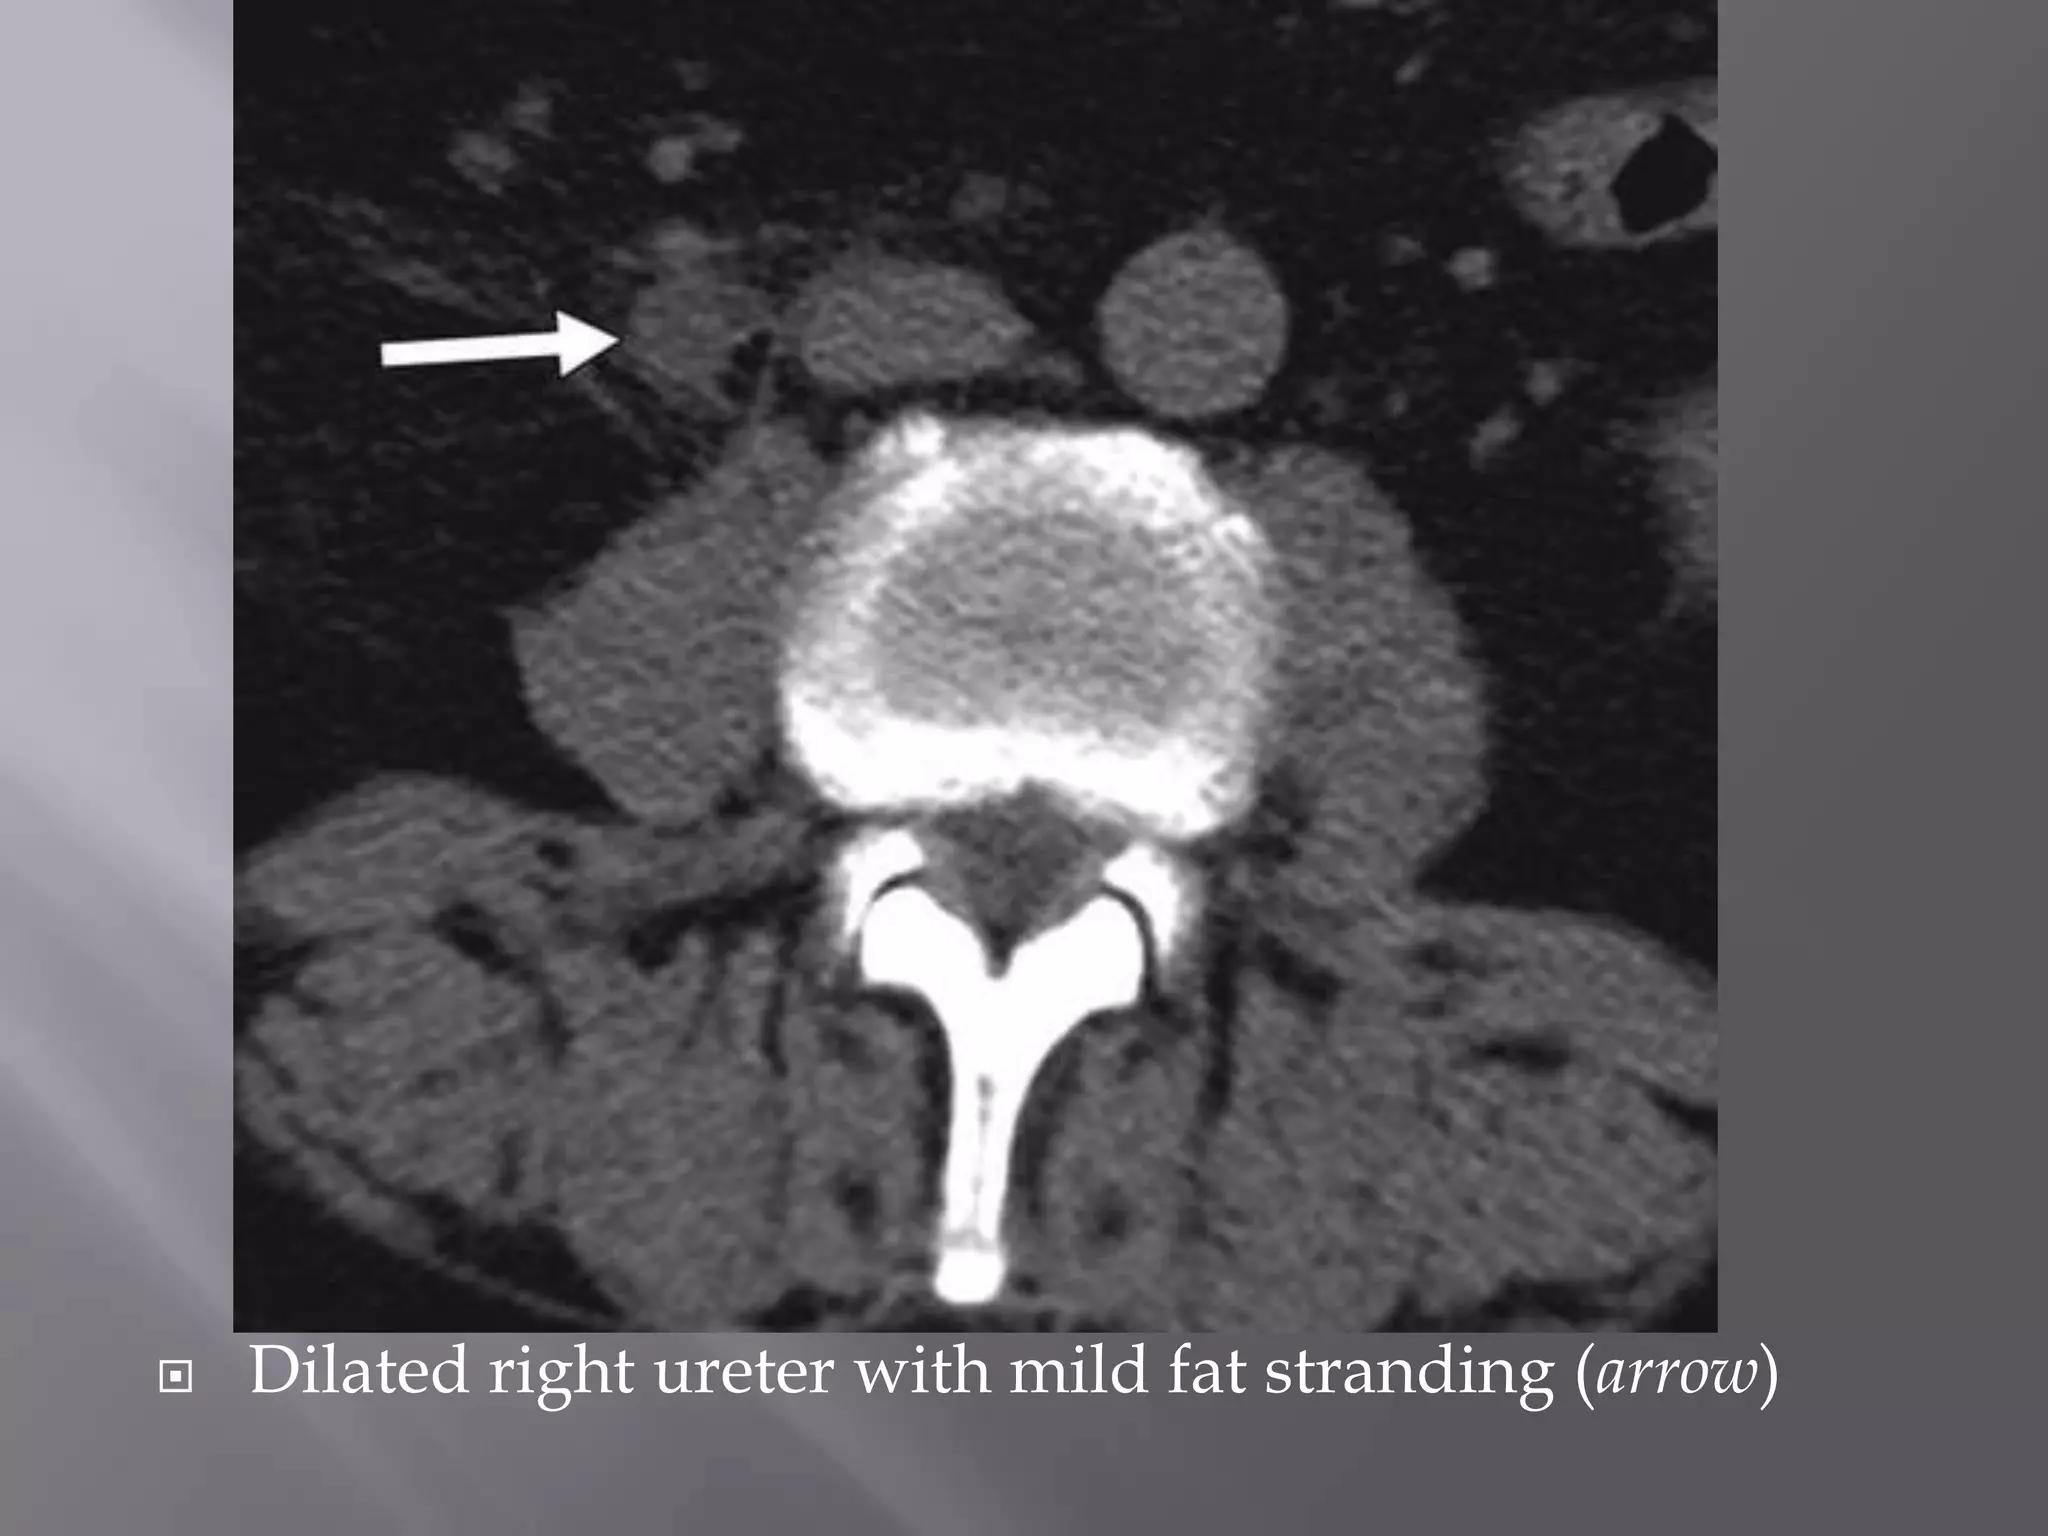

 There is moderate right hydronephrosis (long arrows) and

mild perinephric fat stranding due to edema (short arrow).

 Dilated right ureter with mild fat stranding (arrow)

 There ismoderate right hydronephrosis (long arrows) and mild perinephric fat stranding due to edema (short arrow).

• 41.

 Dilated rightureter with mild fat stranding (arrow)